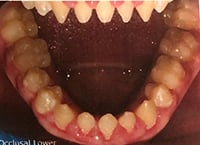

This photo of Courtney's teeth was taken at another Denver-area dental clinic about five years ago, when she was starting high school.

She was born with ectodermal dysplasia, a condition that affects teeth, skin, hair, fingernails and eyes. In the mouth, the condition manifests in misshapen and often-missing teeth. Courtney’s permanent teeth didn’t come in until age 11 and her smile betrayed gaps where teeth should be. Many of the teeth that came in as permanents were conical-shaped — resembling those of a shark.